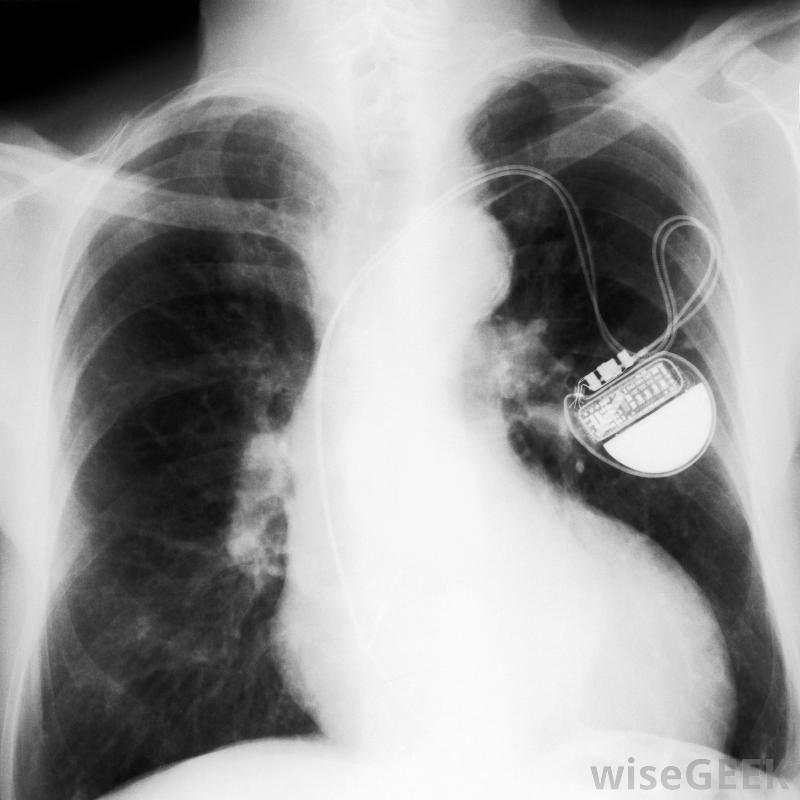

放置过程中,起搏器导线插入胸部左上方的静脉,与放置发生器的区域相同。医生通常使用荧光镜,这是一种X光片,当电线穿过静脉并进入心脏的适当位置时,可以观察这些电线。这通常被认为是一个小手术,而且病人通常不需要全身麻醉。手术通常在诊所或医生办公室进行。

起搏器导线,也叫导线,是一根细线,一端与设备的发电机相连,另一端与心脏相连。每个起搏器可能有两条或两条以上的导线连接到右心房和右心室,有时还连接到左心室。导线的一端有一个电极,电极与心脏相连,以获取心脏的自然电脉冲...